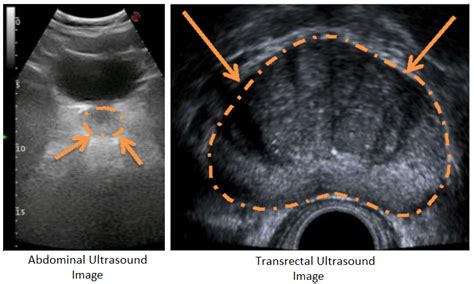

Medical ultrasound visualization of the prostate gland

To accurately determine if an individual’s prostate falls within a normal prostate volume range, medical professionals employ specific diagnostic tools. These imaging techniques provide precise measurements that are far more reliable than a digital rectal exam alone. The common methods include:

Transrectal Ultrasound (TRUS) The gold standard for measuring exact dimensions (length, width, and height) to calculate volume.